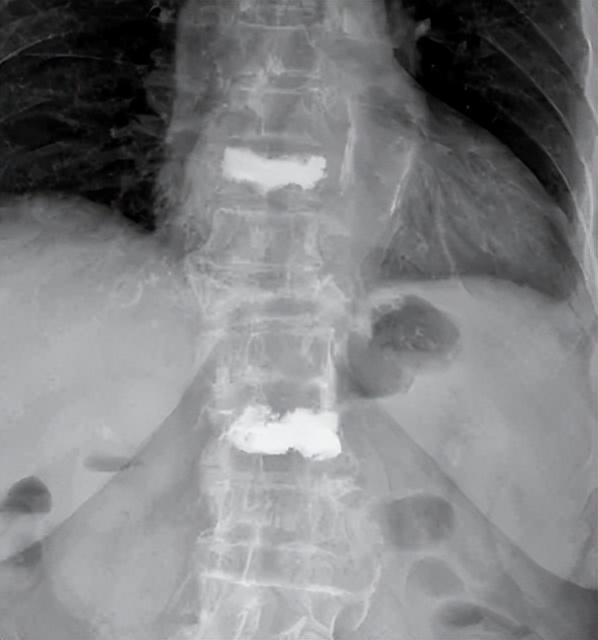

前日脊柱外科的老病患朱奶奶(化名)因“腰背部疼痛,活动困难7天”前来就诊,完善腰椎正侧位见多椎体变扁,核磁示无新鲜椎体骨折,可见胸11、腰1椎体陈旧性压缩骨折,腰3椎体既往因骨质疏松发生病理性骨折已在脊柱外科行腰椎骨折经皮球囊扩张成形术。

患者入院保守治疗效果欠佳,椎体压缩塌陷,汤毅副主任医师团队当机立断选择行胸11椎体骨折经皮球囊扩张成形术。术后疼痛缓解80%以上,患者起床翻身一点都不痛了,术后复查可见骨水泥弥散均匀。